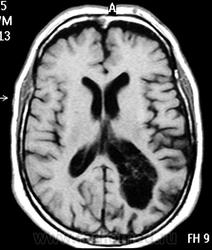

ГМ. Субэпендимома 2. +

Субэпендимома